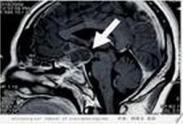

• 空鞍綜合征

628健康網(wǎng)為您分享有關(guān)空鞍綜合征的癥狀,空鞍綜合征的治療方法,空鞍綜合征的預(yù)防知識,空鞍綜合征的癥狀圖片,空鞍綜合征...